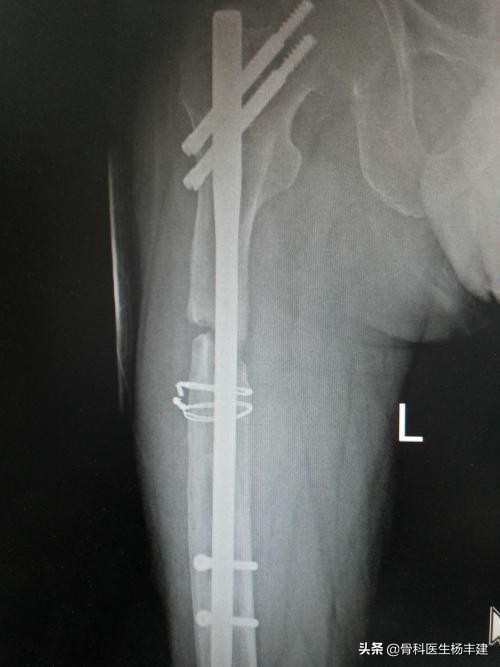

2,股骨粗隆间骨折

股骨粗隆间骨折是老年人最常见的骨折之一,杨医生之前的科普文中也曾用讨论。由于股骨近端存在颈干角,如果使用钢板固定,主要承受折弯的力量。特别是内侧缺乏支撑的情况下,很容易发生钢板断裂。曾经有国外的论文报道,股骨粗隆间骨折使用钢板固定后,发生钢板断裂的概率接近40%,所以目前主流的观点认为股骨粗隆间骨折应该使用髓内钉进行内固定。

锁骨骨折后钢板断裂怎么办,股骨骨折钢板断裂原因分析

使用钢板固定粗隆间骨折,出现钢板断裂,这种例子屡见不鲜